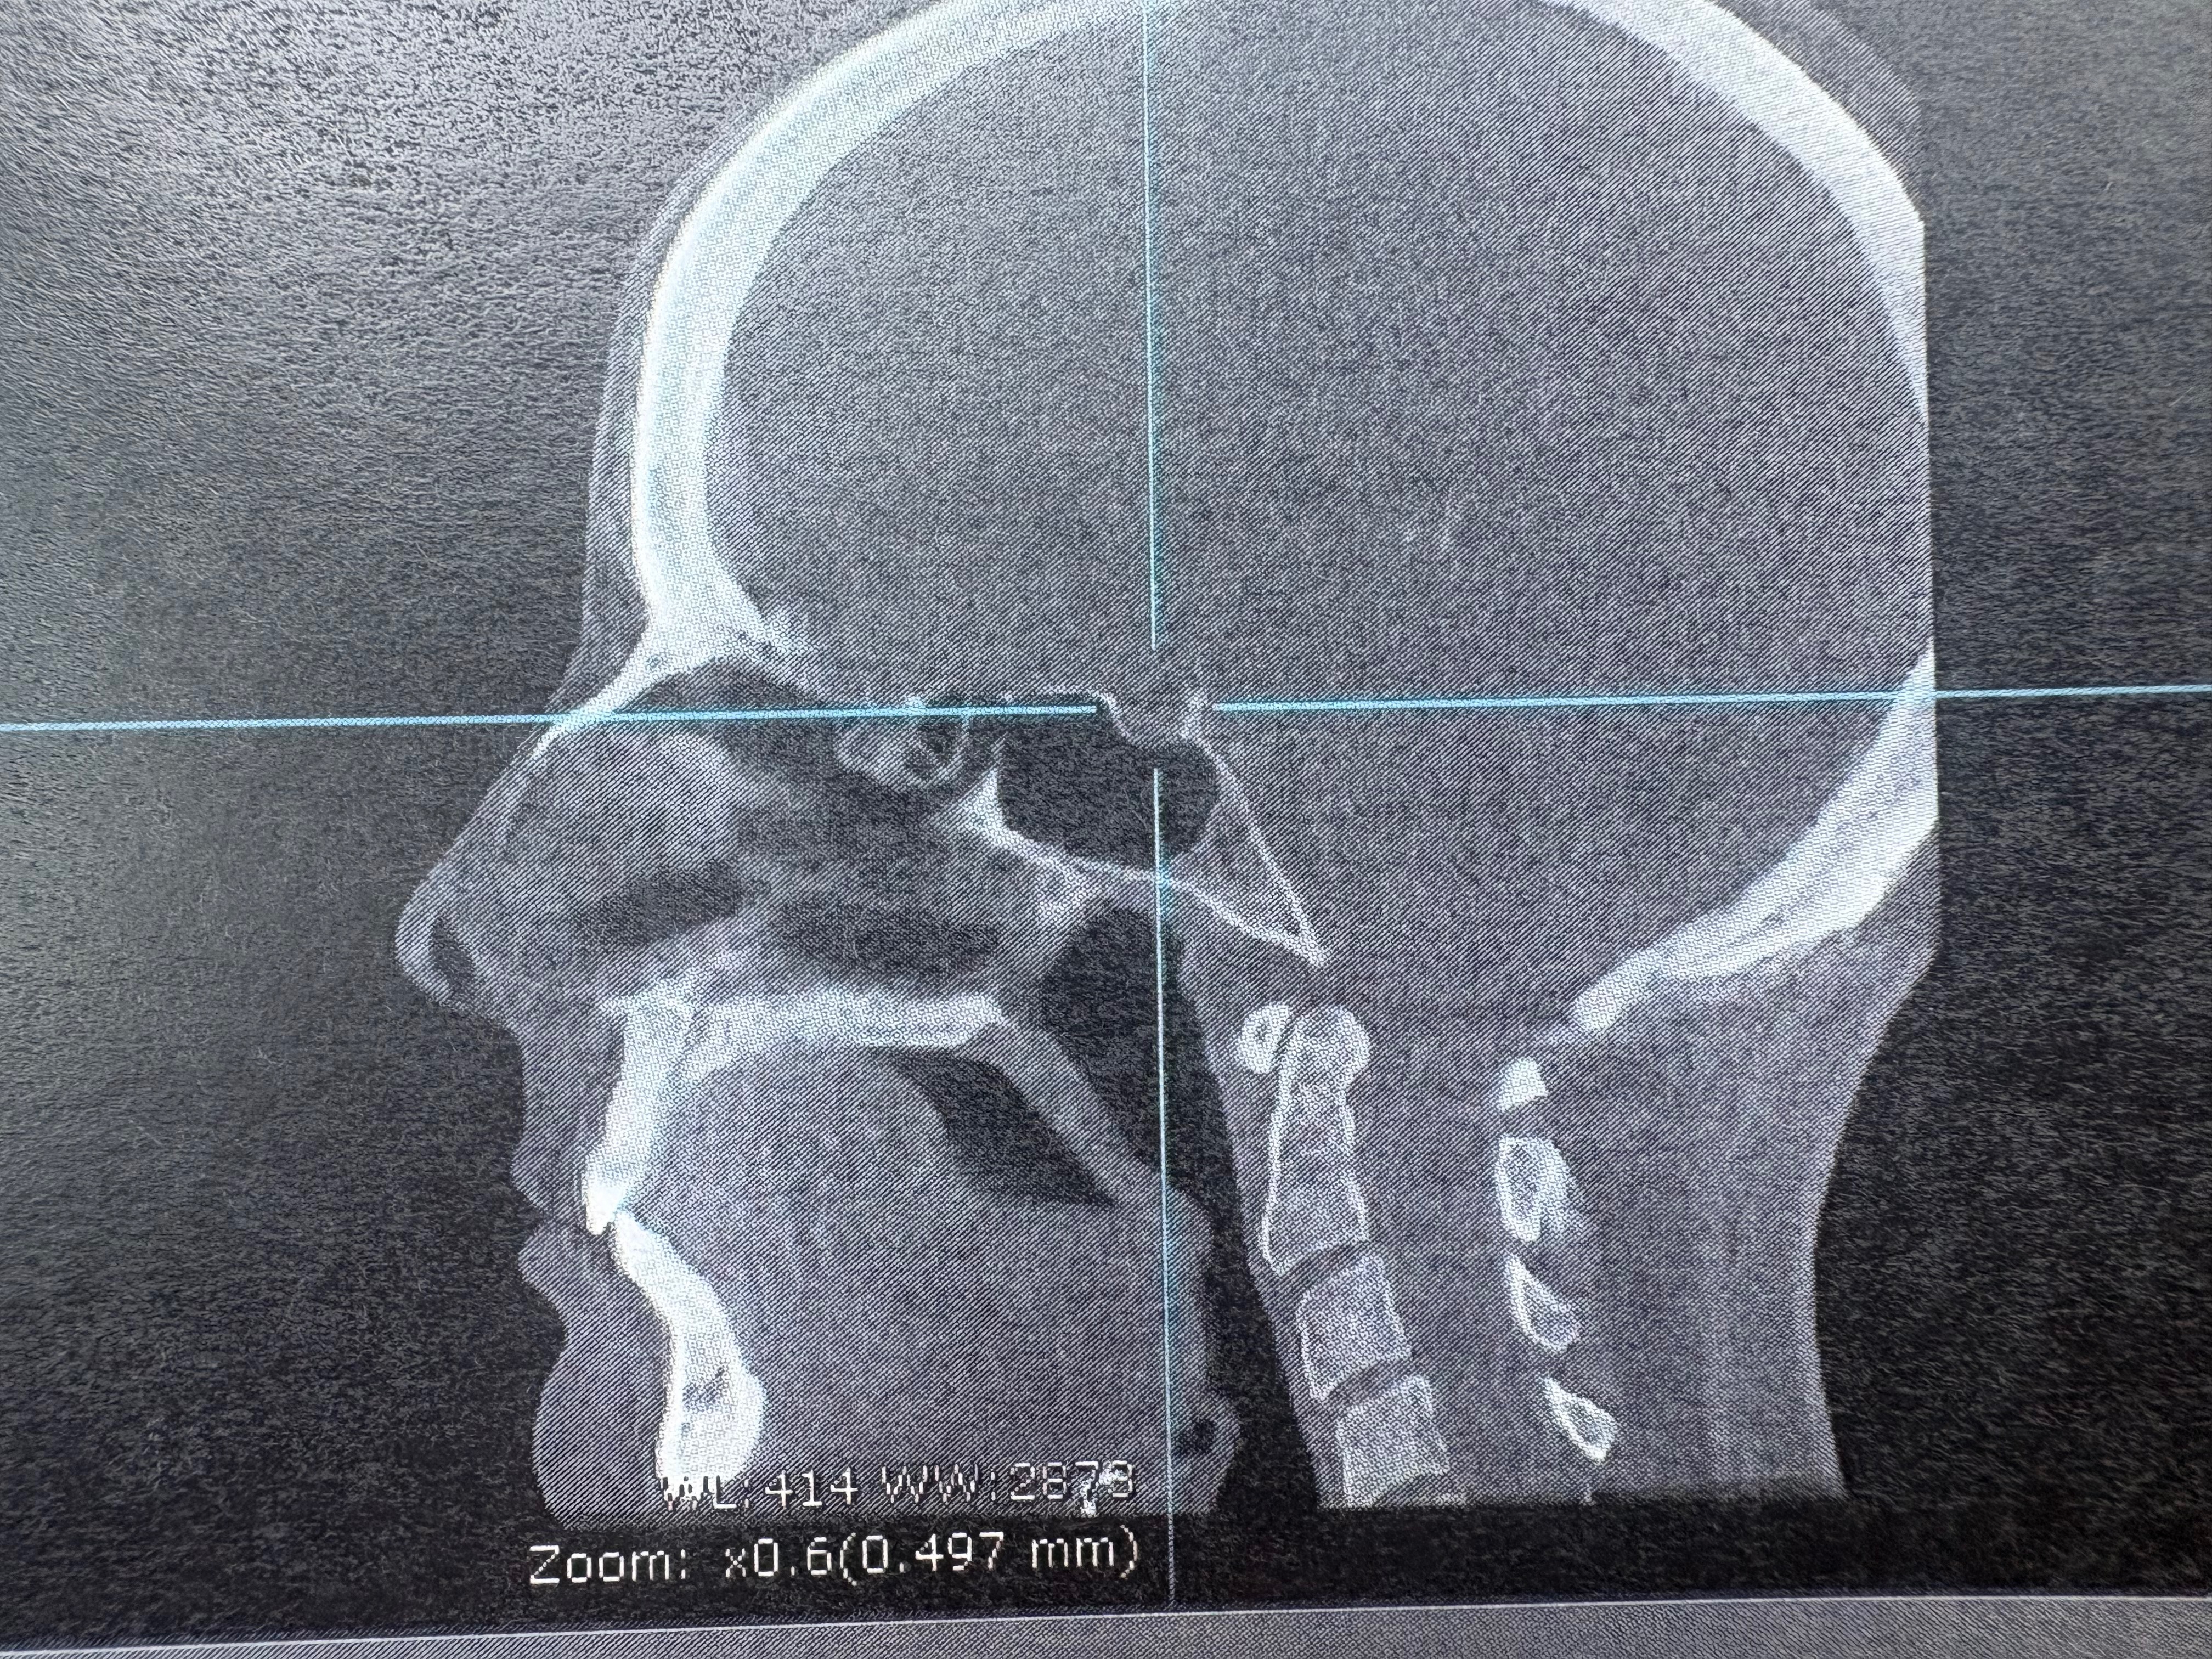

Thank you so much for your help. I have been seeing a Myofunctional therapist who is helping me out as much as she can but with little to no space in my mouth for my tongue there isn’t much she can do. I have also attached the out of network surgeon’s consultation and CTCB scan. I will also continue to file claims and grievances with Kaiser with hopes this can be solved that way but it’s been an absolute nightmare and I’m running out of time.